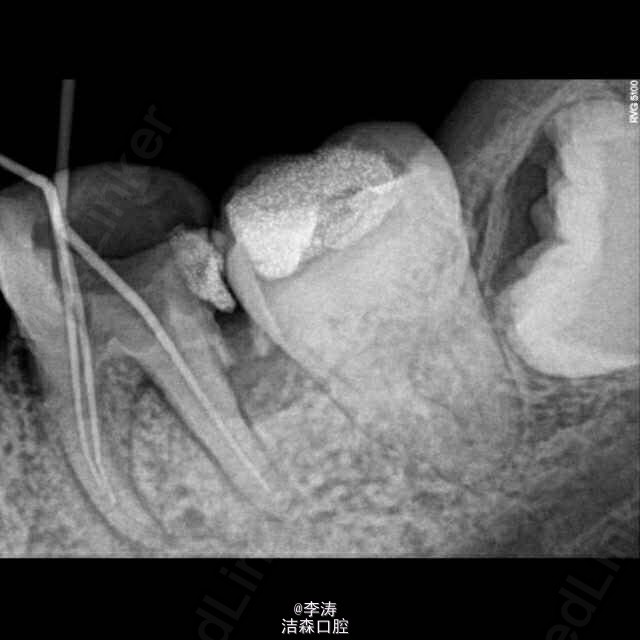

根管预备形成台阶1例

36牙根管治疗,近中根略弯曲,先疏通至15号,k3冠向下法预备,预备时形成台阶,然后怎么预弯都下不去! 太弯根管的还是应该使用手扩,特别是k3,弯曲根管尽量不用,容易形成台阶。另外预备过程中不能使用暴力!!